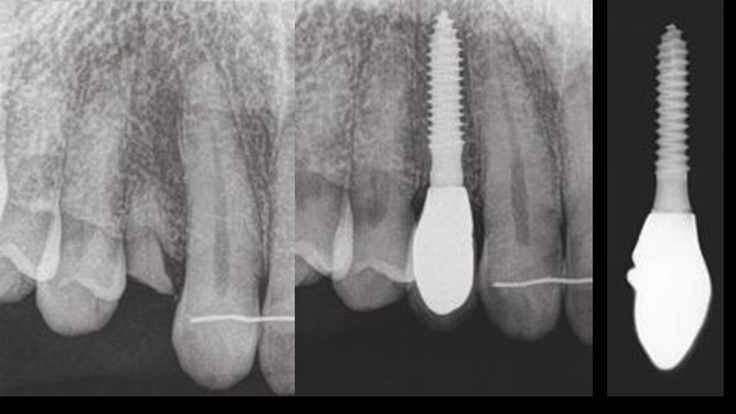

“AnyRidge is perfect for the anterior esthetic zone due to its strong initial stability & fast osseointegration.

Plus, KnifeThread® ensures space maintenance when using the PET/Socket Shield/Root Membrane Technique, showing excellent bone growth.”

Thanks to MegaGen’s unique KnifeThread® and super self-tapping design, better initial stability can be attained in any compromised bone situation.

The design enables bone condensing, gentle ridge expansion, maximized compressive force resistance, and minimized shear force production.